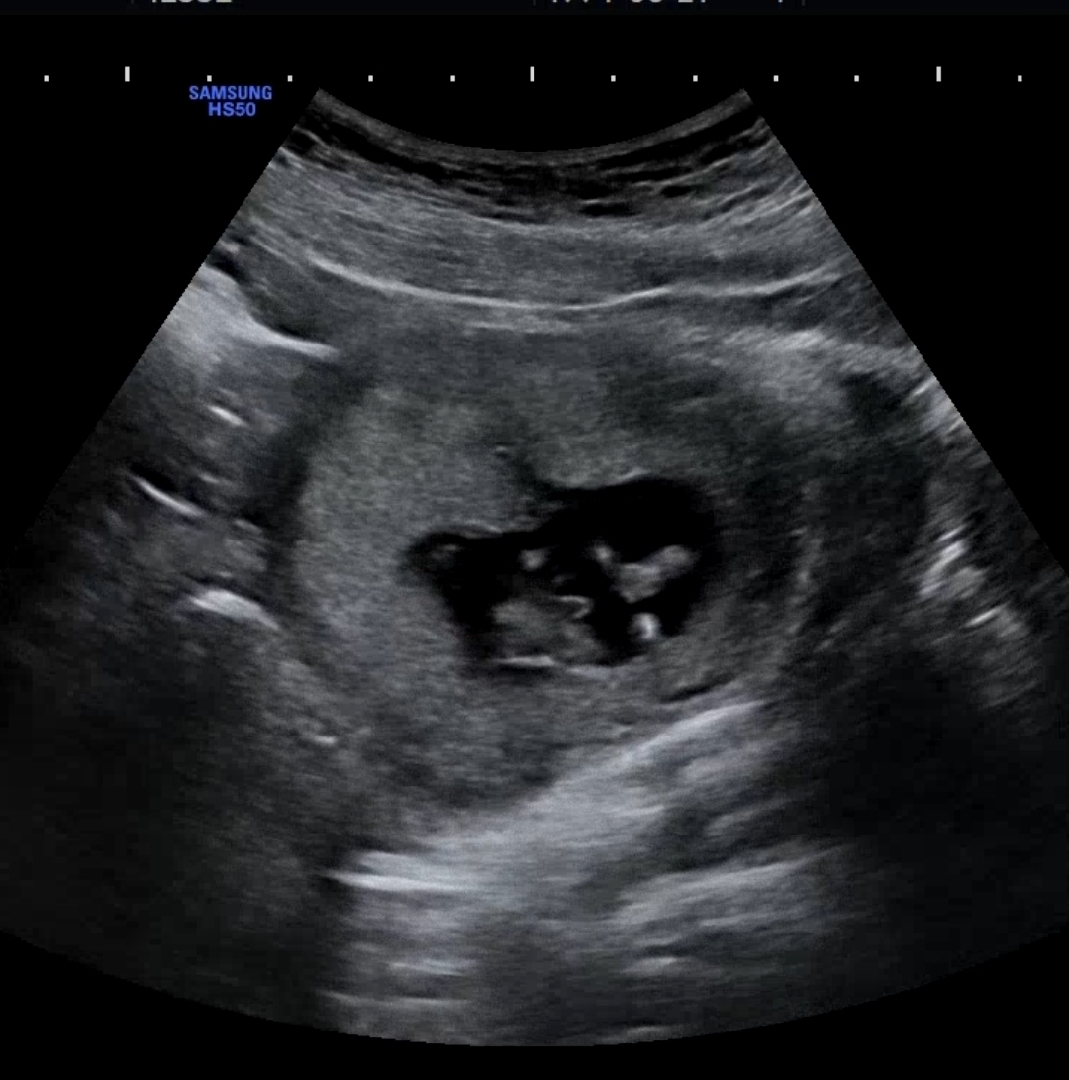

12주4일 이정도면 아들 확정인가요😂

저는 아들파,남편은 딸랑구파인데 서브병원에서 가운데 뭐보이내요~~거의 아들같아요ㅎㅎ 하셨는데 변화없겠죠?!